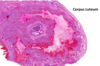

corpus leteum

- corpus luteum צהבהב)

מה תפקידו של הגופיף הצהוב (הזקיק שנשאר בשחלה לאחר שהביצית יוצאת) במהלך ההריון?

תומך בזמן ההיריון, מפריש אסטרוגן ופרוגסטרון, בערך 5 חודשים לתוך ההריון

אם אין הריון הוא מתנווץ ונהיה גופיף לבן- רקמת צלקת.

מה קורה בכל ביוץ שאין בו הריון?

מגיעים פיברובלסטים ומאקרופאגים שאוכלים את התאים, הפיברובלסטים מפרישים קולגן שיוצר רקמת צלקת- גופיף לבן.

כל ביוץ ללא הריון משאיר צלקת.